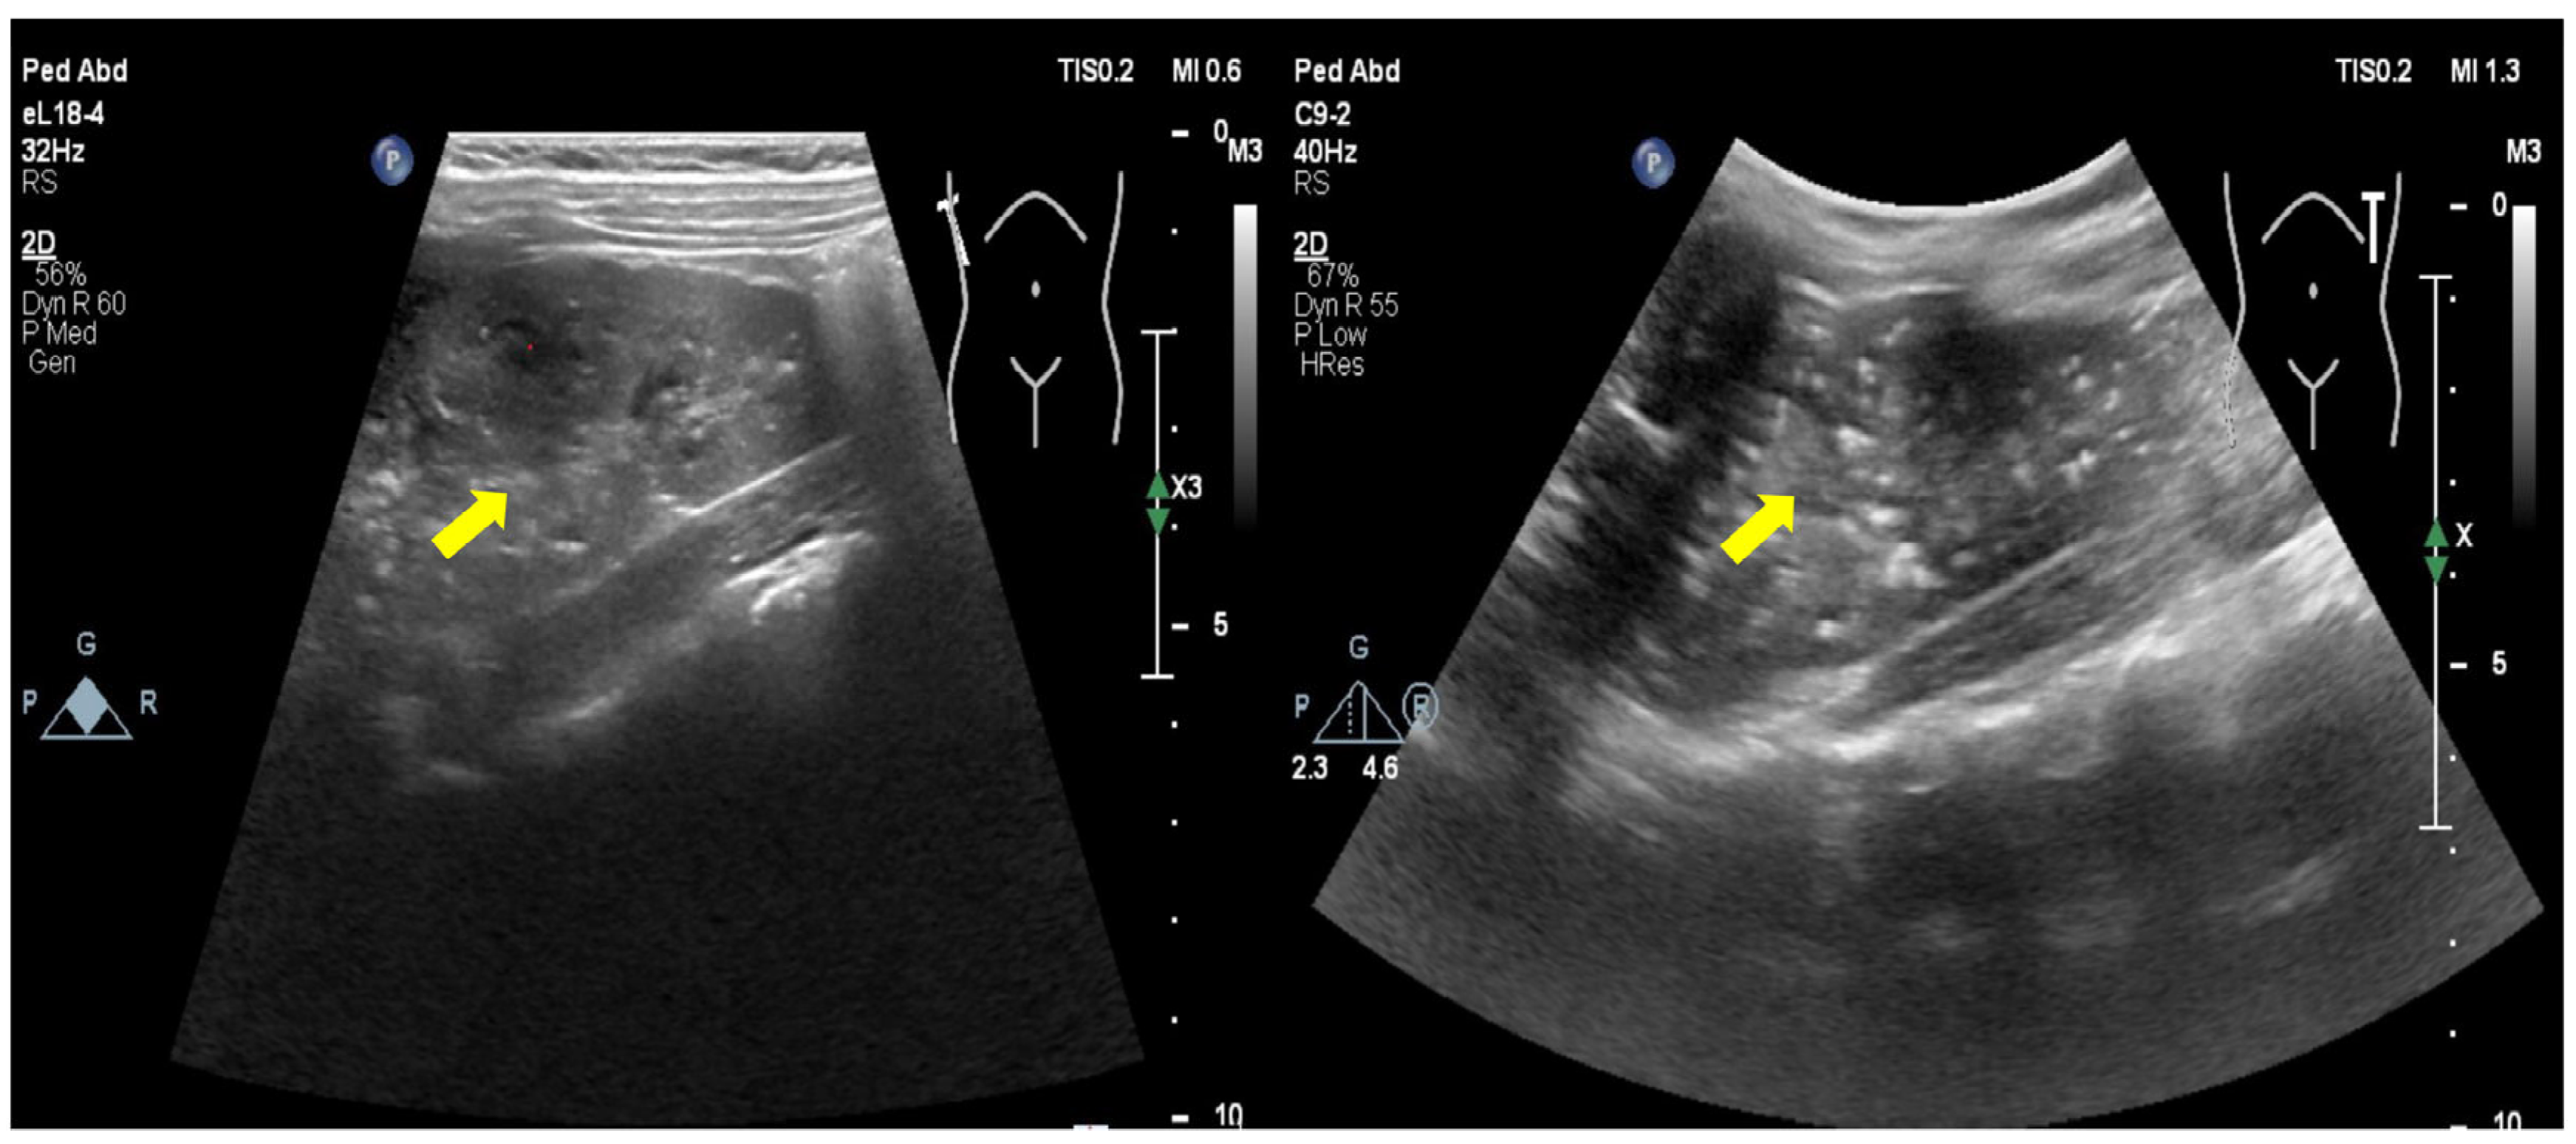

3.1. Clinical Information